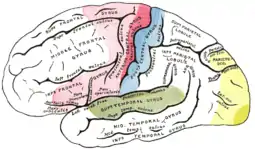

Le néocortex est divisé en lobes frontaux, pariétaux, occipitaux et temporaux, qui effectuent des tâches distinctes. Par exemple, le lobe occipital contient le cortex visuel primaire et le lobe temporal contient le cortex auditif primaire. Des divisions plus fines du cortex permettent d'isoler des fonctions plus spécifiques. Chez l'humain, le lobe frontal contient les aires dévouées aux habilités qui sont les plus développées chez notre espèce, comme le traitement complexe du langage, localisé dans le cortex préfrontal ventrolatéral (l'Aire de Broca). Les fonctions sociales et émotionnelles sont situées, chez le primate (dont l'homme), au niveau du cortex orbitofrontal.

- Aire motrice primaire

- Aire motrice supplémentaire préfrontale

- Aire sensorielle primaire

- Aire d'association sensorielle

- Aire visuelle primaire

- Aire auditive primaire